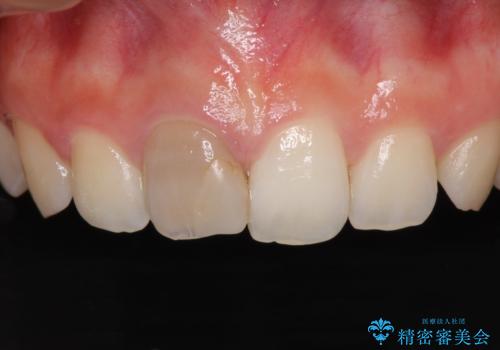

ぶつけて変色した前歯 オーダーメイドタイプのオールセラミッククラウン

- 中学生の時にぶつけて神経を取り除いた前歯の変色が気になるとのことで来院された患者様です。

レントゲン写真より、歯根の炎症が認められなかったため、ファイバーコアによる土台築製後、オーダーメイドタイプのオールセラミッククラウンにて補綴することとしました。